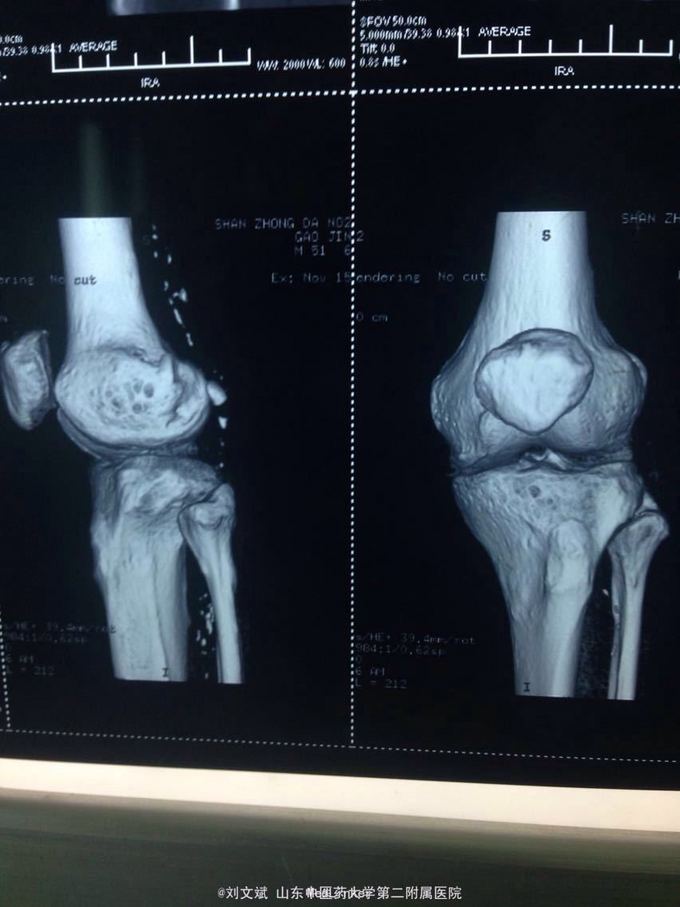

男性51岁,左膝关节疼痛不适10余年。因症状较轻,不影响活动,未曾系统诊治。一月前因扭伤致疼痛加重,拍片检查,见股骨远端骨质异常,进一步行CT示股骨髁占位病变,考虑骨囊肿。既往有高血压,糖尿病病史。近期无低热,体重下降。

诊断:左股骨远端占位 因皮质完整,行手术开窗刮除,自体髂骨及同种异体骨混合植骨填充治疗。切取组织送病理检查

刮除占位组织如图所示,送病理检查了,结果还没回来。 没有全身症状,像是原发灶,骨皮质完整,没有明显骨膜反应请专家们看看,什么可能性比较大? 补上病理结果和术后片子